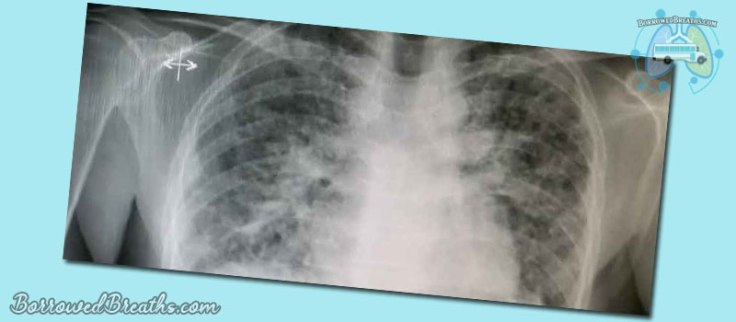

You may also hear this condition referred to as “honeycombing” or “honeycomb lung.” The reason for this is that the scarring can resemble the honeycombs made by bees. Not the perfect hexagons bee keepers use on honey farms. But rather the natural haphazard product of bees out in the wild.

I.P.F is what I was diagnosed with after honeycombing was discovered in my lungs and no definitive cause could be determined. If the cause had ever been discovered, then my diagnoses would have been changed.